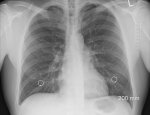

«Плеврит описывает состояние, при котором воспаляются два больших тонких слоя ткани, которые отделяют ваши легкие от грудной стенки. Эти слои также называют плеврой. Наиболее частым симптомом этого состояния является острая боль в груди, которая усиливается при дыхании», - говорит врач-терапевт Ирина Андреева специально для МедикФорум.

Между плеврой находится щель, называемая плевральной полостью. Когда вы вдыхаете, эта жидкость позволяет плеврам плавно скользить друг относительно друга. У человека с плевритом плевра воспаляется и трется друг о друга каждый раз, когда ваше легкое расширяется, вызывая боль в груди.

У некоторых пациентов с плевритом может наблюдаться накопление жидкости, называемое плевральным выпотом.